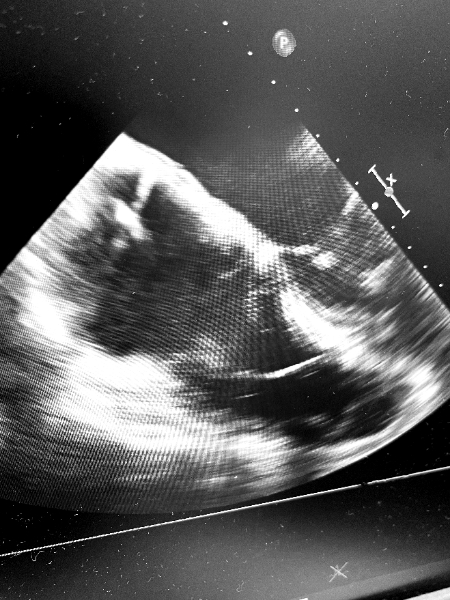

Our first *3* implants in the @AbbottCardio #ASCEND trial yesterday! The lead handles beautifully and we got fantastic LBB capture in all patients. #EPeeps #DontShocktheHis 😂😂

Transvenous, Extraction, Leadless: Opportunities in the New Era of Leadless Pacemakers Dr Samira Teeri et al share a case demonstrating a successful upgrade from a single-chamber to a dual-chamber leadless pacemaker. okt.to/CWq1xF @samirateeri @CyrusHadadiMD #EPeeps